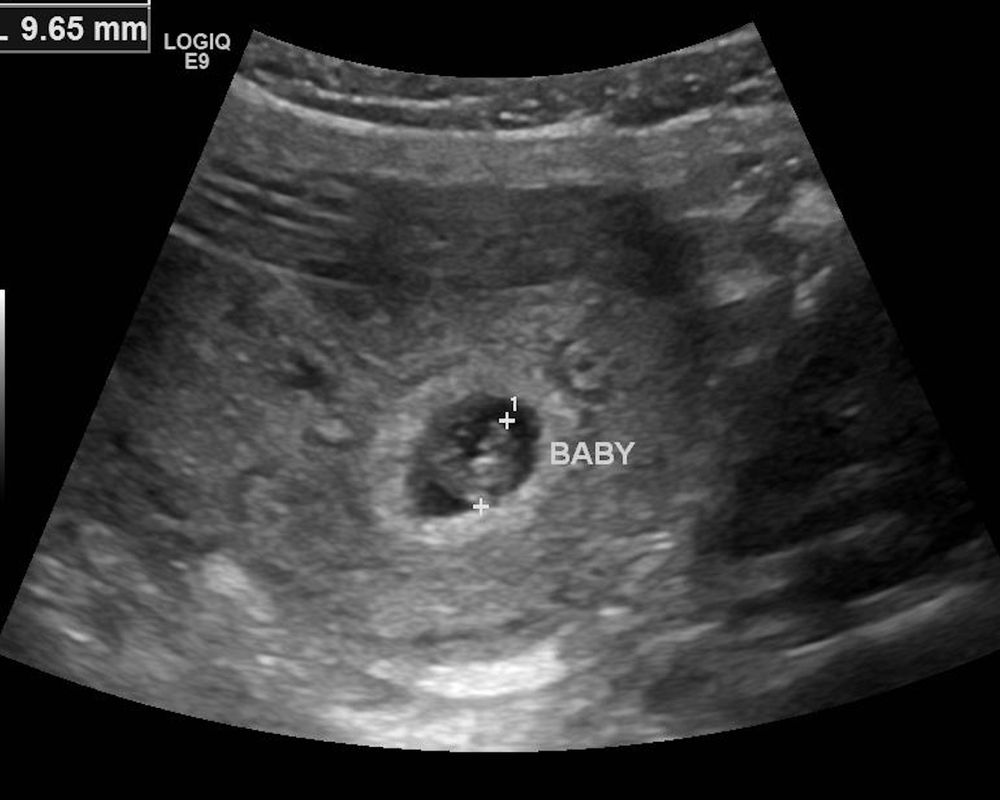

Маленькое плодное яйцо + фото

Первое узи с эмбрионом Мелкие кисты в цервикальном канале